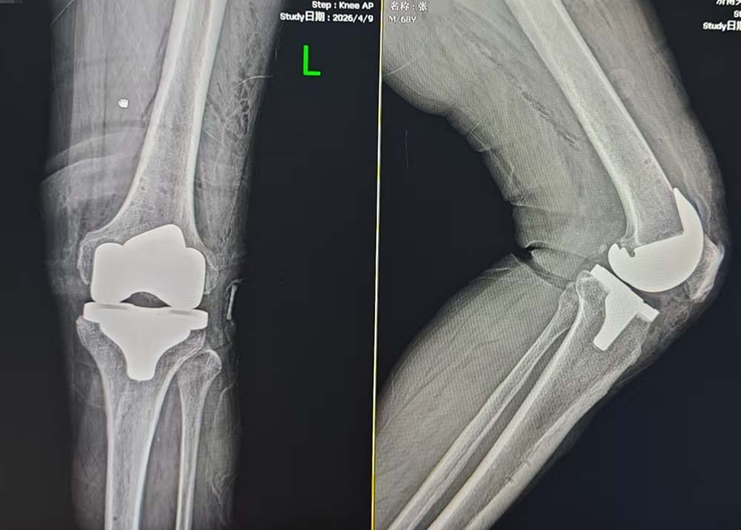

2026年2月、4月,张大爷分两次在该院接受了Mako机器人辅助下的左膝、右膝全膝关节置换手术。术前Mako机器人依据张大爷的检查报告,生成符合生理结构的3D虚拟模型,制定详细的术前规划,术中机器人经过精确计算,辅助医生完成截骨、安装假体等手术操作,精准度至0.1毫米,有效减少对患者的创伤,让手术更安全、更精准。